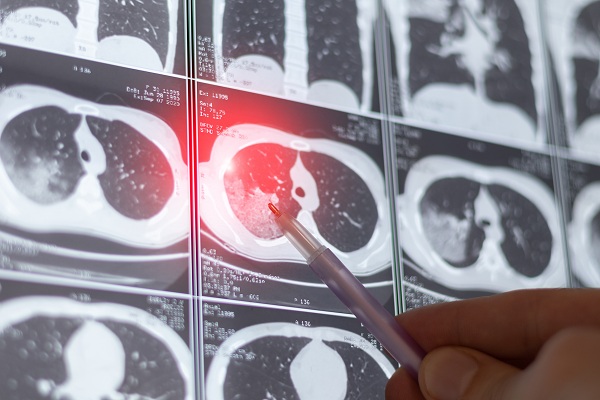

She got the screening that August, and the radiology report came back two days later.

“Based on that first CT scan, they found a nine-millimeter nodule in the upper right lobe of my lung,” Geer said. “In the overall scheme, it was on the small side, but notable.”

A follow-up scan that fall showed the nodule was growing, and Geer was referred to Salem Hospital’s Dr. Tieu.

Geer continued to get follow-up CT scans and meet with Dr. Tieu.